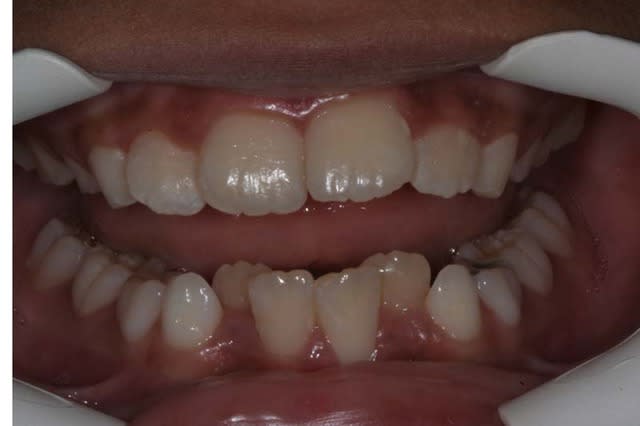

Avant TTT.

à suivre Bjc.

la coloration des dents est assez remarquable

P.S.: j'avais à l'époque un Fuji mono-objectif

les photos de la contention ont été prises avec un Canon 1000 objectif Macro

les couleurs ne sont pas tout à fait les mm.

mais les dents ont gardé la mm. forme et les taches sont reconnaissables

@+ Bjc.